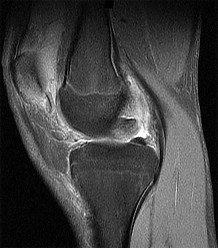

A 68-year-old female is evaluated 6 weeks after an uncomplicated primary total knee arthroplasty (TKA). Despite dedicated daily physical therapy, her range of motion remains stalled at 10 to 70 degrees. Radiographs reveal well-fixed and well-aligned components without signs of loosening. What is the most appropriate next step in her management?

Explanation

Postoperative stiffness after TKA is a well-recognized complication. The optimal timing for manipulation under anesthesia (MUA) is generally between 6 to 12 weeks postoperatively when conservative measures (aggressive PT) have plateaued or failed. Performing an MUA within this window is highly effective for breaking up immature adhesions. Waiting beyond 12 weeks decreases the success rate due to the maturation of dense intra-articular scar tissue.